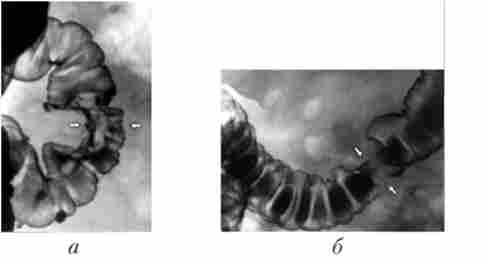

Основним методом рентгенологічного дослідження товстої кишки служить іригоскопія (Рис. 14.5). Вона полягає в ретроградним введенні контрастної речовини через пряму кишку за допомогою апарату Боброва, що дозволяє домогтися тугого наповнення органу і детально вивчити положення, форму, розміри і особливості контуру товстої кишки. При цьому також використовують метод подвійного контрастування, т. Е. Другою

етап ирригоскопии. Другий етан виконується після спорожнення кишки від ренгеноконтрастной суспензії. Дослідження проводять при дозованому заповненні кишки повітрям, також використовуючи апарат Боброва. На тлі подвійного контрастування стає можливим детальне вивчення рельєфу слизової оболонки.

Рентгенологічна картина раку ободової кишки

Мал. 14.5. Рентгенологічна картина раку ободової кишки

(Іррігограмми):

а - стрілками вказано дефект наповнення; б - стрілками вказано ділянку циркулярного звуження просвіту кишки

Інтерпретація рентгенологічної картини заснована на тих же принципах, що і аналіз результатів рентгенологічного дослідження стравоходу, шлунка і дванадцятипалої кишки із застосуванням перорального контрастування. При раку ободової кишки виявляють ділянки звуження товстої кишки, визначають «ніші», дефекти наповнення, зміни рельєфу слизової оболонки і оцінюють рухову активність кишки.

Слід пам'ятати, що при тугому наповненні органу під час ірріго- скопии просвіт товстої кишки виглядає значно ширше, ніж при пероральному контрастировании.